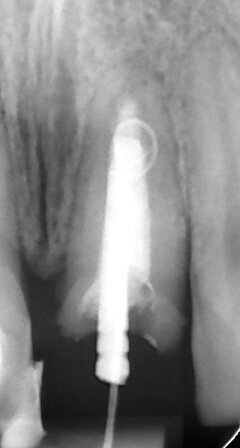

Apexification

In order to prevent extrusion of root canal filling material in immature teeth with open apices, MTA is used as an apical plug. The results of many studies have shown that MTA induced apical hard-tissue formation more often and its use was associated with less inflammation than with other test materials (Figs. 2a–g).[4]

Fig. 2a: (a) Endodontically treated tooth with fistula. (b) After retreatment, the tooth showed an open apex. (c) MTA application with the MAP System and PD MTA White. Condensation of the MTA with pluggers (d) or paper points (e). (f) MTA plug. (g) Post-op radiograph showing the MTA plug and the reconstruction with a fibre post.

Fig. 2c: (a) Endodontically treated tooth with fistula. (b) After retreatment, the tooth showed an open apex. (c) MTA application with the MAP System and PD MTA White. Condensation of the MTA with pluggers (d) or paper points (e). (f) MTA plug. (g) Post-op radiograph showing the MTA plug and the reconstruction with a fibre post.